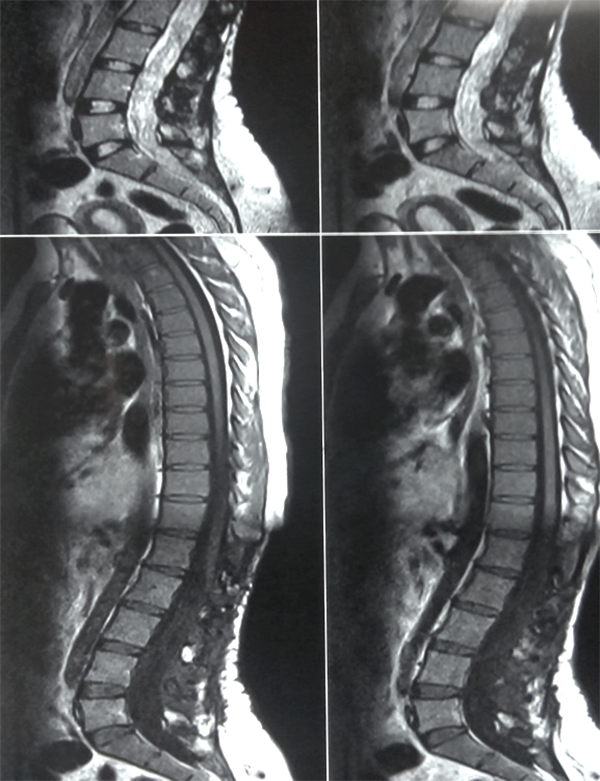

Es evidente que el límite entre el tejido medular y tumoral en las lesiones como los astrocitomas es indiscernible lo que dificulta la posibilidad de resección completa; en los tumores como los ependimomas esta diferencia es más franca y permite seguir un plano de disección seguro (Figuras 3, 4 y 5). Lo anterior condiciona nuestros resultados como han puntualizado diversos autores.5,8 El estado general previo a la cirugía requiere de una valoración juiciosa de las posibilidades de resección. Por ejemplo, el caso 12 (Figura 6) es una paciente portadora de Enfermedad de Von Hippel Lindau, Hemangioblastoma cervical biopsiado en otra institución del exterior del país, fijación de columna cervical y sindrome de Cushing por exceso de medicación corticoidea cuya cirugía debió suspenderse en dos oportunidades por la disminución de su capacidad ventilatoria. Con estos antecedentes y la delgada capa de tejido medular evidenciada intraoperatoriamente se optó por una resección subtotal. A los cuatro meses de la cirugía la paciente recuperó la marcha autónoma y demás parámetros clínicos.

Figura 5: Caso 1. Astrocitoma Pilocítico cervical. A: preoperatoria. B: Cifosis 2 años post resección. Marcada “atrofia” medular.

Figura 6: Caso 12. Hemangioblastoma cervical. Ocupa la mayor parte del cordón medular marcado con círculo.